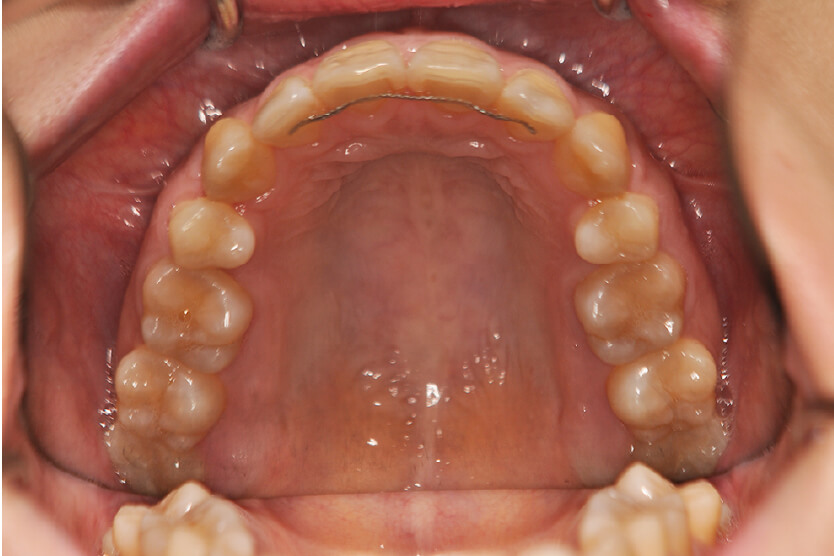

| 治療内容の詳細 | 初診時21歳の女性で、八重歯、歯のがたつき主訴として来院されました。 検査の結果、上下顎前歯部叢生を伴うアングルⅡ級1類不正咬合と診断しました。 治療としては、上下顎左右第一小臼歯を抜歯し、セルフライゲーションブラケット装置(デーモンシステム)とマウスピース矯正装置(インビザライン)で歯の配列を行いました。 治療期間は、1年4か月でした。 |